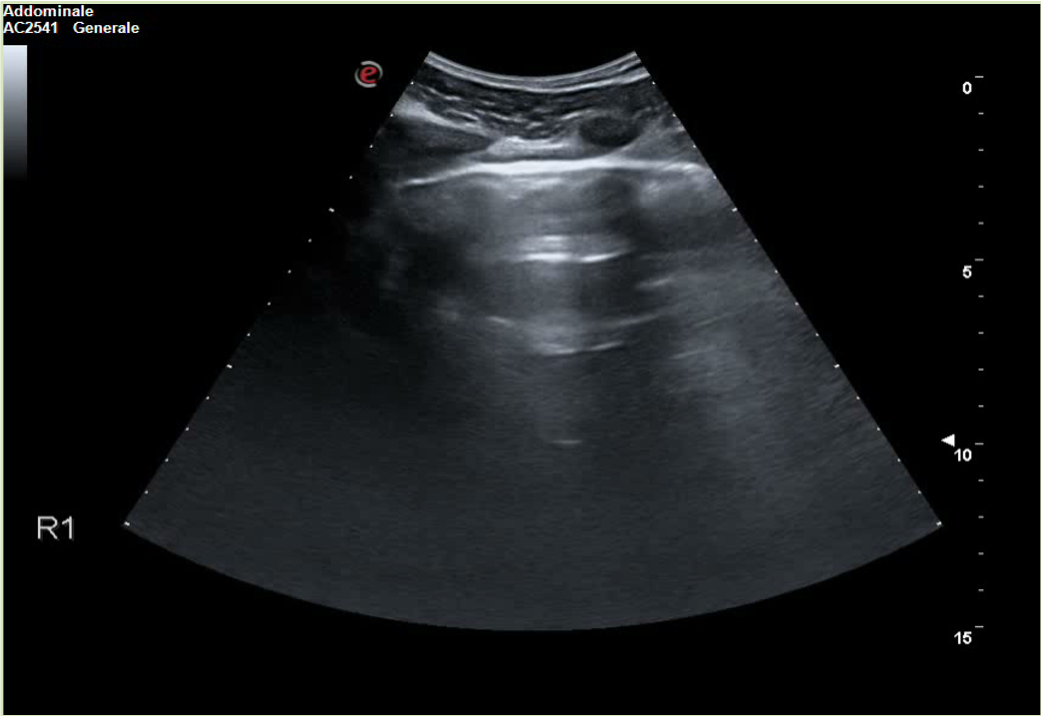

A 30-year-old man presents to the emergency department (ED) due to syncope. For the last 10 days he had had fever, cough and dyspnea. At the ED his peripheral oxygen saturation was 86%, BP 130/80, HR 88bpm, RR 20 /min and his temperature 37.4°C. He was given oxygen via a mask. Chest CT was performed and later lung ultrasound (LUS) was performed in 12 areas longitudinal/oblique views using a convex array probe followed by a linear array probe for details (figure 1).

The patient tested positive for SARS-COV-2. On day 2 after admission the patient’s condition deteriorated, and he was transferred to the ICU. Another chest CT was performed. We show the ultrasound and CT images with corresponding legends (image 1-7 + video 1) and discuss the findings in relation to the diagnostic work-up of COVID-19 pneumonia.

On imaging, initial lesions are usually peripheral because SARS-COV-2 attacks the small distal airways. Several reports have described the findings in chest CT. Most commonly few, small, segmental ground glass opacities are seen peripherally and basal. These may deteriorate to become bilateral and multisegmental and finally consolidation and/or ARDS. Most common LUS signs are: vertical pleurogenic artifacts with varying degree of intensity (from few to confluent). These alternate with clear demarcation to A-lines in the same area, especially in the mid- and upper lung. Pleural thickening, sometimes marked, due to the presence of numerous, small subpleural consolidations. Lobar or translobar consolidations of large size and minimal pleural effusions. The LUS features match with the site and kind on CT.

LUS is an examination, which can be carried out bedside. It may provide early information of presence of diffuse multifocal pneumonia (as in COVID-19) and its deterioration (enlarging consolidations). By doing LUS in cases with COVID-19 pneumonia, transport of patients through the hospital and unnecessary exposure of staff and other patients is avoided. Similar LUS signs as the ones described have been observed in other kinds of viral epidemic pneumonia. If they, individually or in combination, have some specificity for COVID-19 pneumonia it should be established with further appropriate studies.